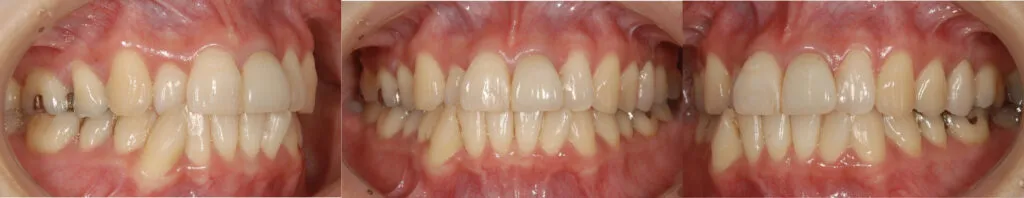

症例7

- 主訴

- 矯正して前歯をきれいにしたい

- 治療内容

- 矯正治療とセラミックによる修復治療

- 治療費

- 120万

- 治療期間

- 2年半

- 通院回数

- 50回

- 想定されたリスク

- 矯正治療後の後戻り

- コメント

- 歯並びが改善され、セラミック治療によって審美性が改善されました

before

after